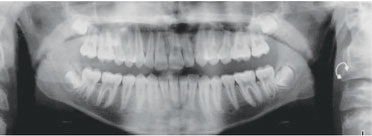

Fig. 6: Three-month progress records, with weekly aligner changes.

Fig. 7: Six-month progress records, with weekly aligner changes. Class I molar and canine relationship was achieved, but the transverse and posterior vertical dimensions still needed correction.

Fig. 8: End of mandibular advancement phase, with weekly aligner changes for 12 months. (Upper and lower: 23, then 26, each.)